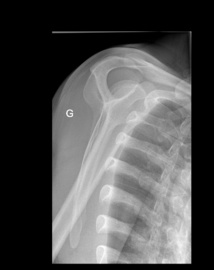

Pour preuve, voici les images observées chez un patient présentant depuis plusieurs semaines des douleurs scapulaires antérieures apparues suite à un traumatisme !

Avant de faire le diagnostic ultrasonore de la fracture, ce patient a eu des radiographies de l'épaule et une IRM qui n'ont décelé aucune anomalie.